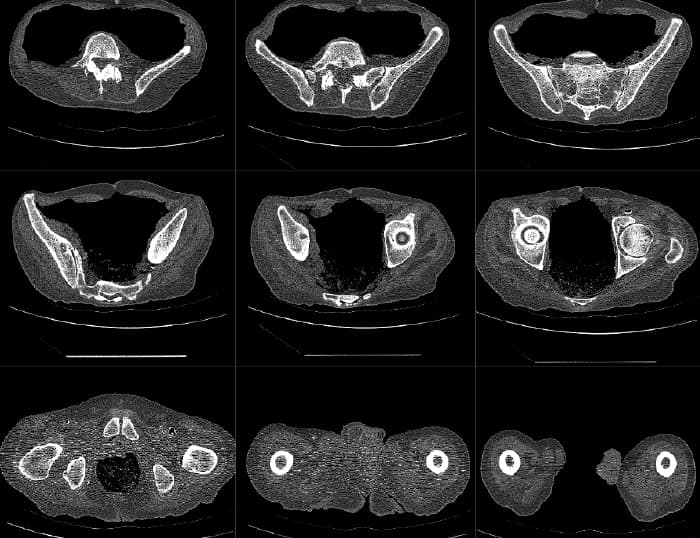

Mako Robotic-Arm Assisted Technology provides you with a personalized surgical plan based on your unique anatomy. First, a CT scan of the diseased joint is taken. This CT scan is uploaded into the Mako System software, where a 3D model of your hip is created. This 3D model is used to pre-plan and assist your surgeon in performing your total hip replacement.

Step 1. Hip CT Scan